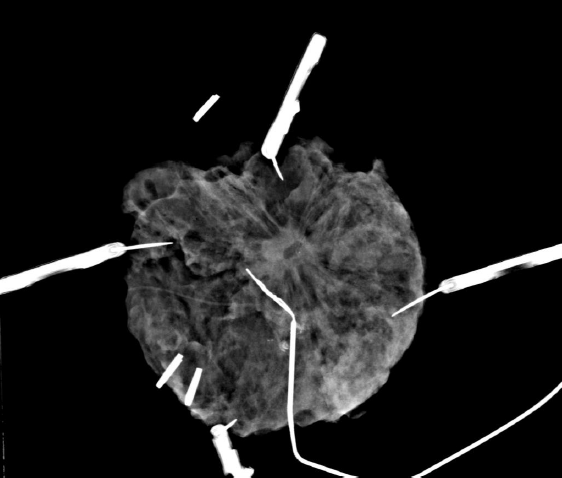

Cliché de mammographie avec repérage de la Tumeur et radiopièce correspondante

avec la tumeur au centre de l'image